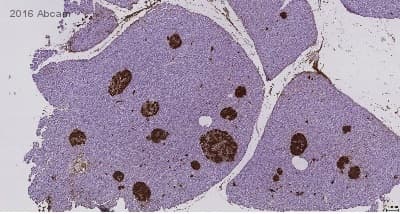

Anti-Insulin antibody [E2E3](ab9569)

Mouse Monoclonal Insulin antibody. Suitable for IHC-P and reacts with Human samples. Cited in 6 publications. Immunogen corresponding to Full Length Protein corresponding to Pig INS.

Applications IHC-P

Species Reactivity Human